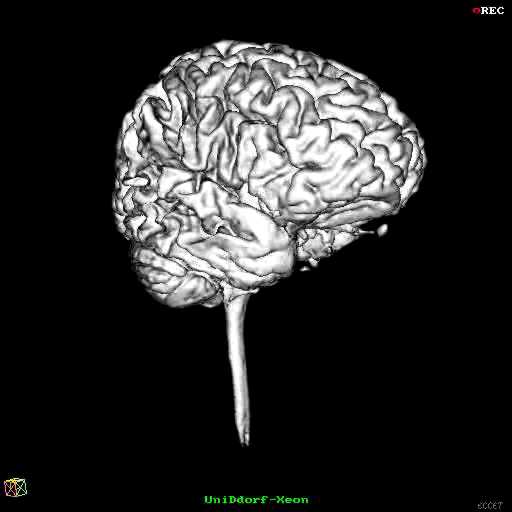

Hirnstamm Der so konstruierte Hirnstamm ist in den folgenden Bildern gelb dargestellt. Die beiden blauen Ringe markieren diejenigen Schichten, zwischen denen der Hirnstamm durch Interpolation gewonnen wurde. Das Kleinhirn ist weiß dargestellt. Die Kleinhirnschenkel werden zum Volumen des Kleinhirns gezählt.